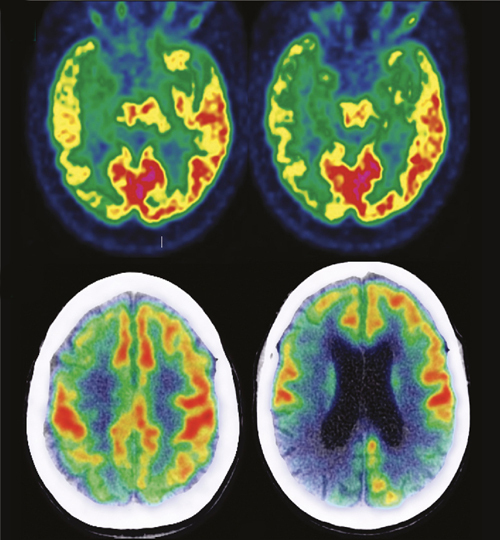

Il s’agit d’un anticorps monoclonal ciblant les plaques amyloïdes cérébrales* développé par le laboratoire Biogen. Son effet sur la charge cérébrale de ces lésions a été montré (en utilisant des techniques telles que la tomographie par émission de positons) par les dernières études de phase III, mais son bénéfice clinique reste controversé.